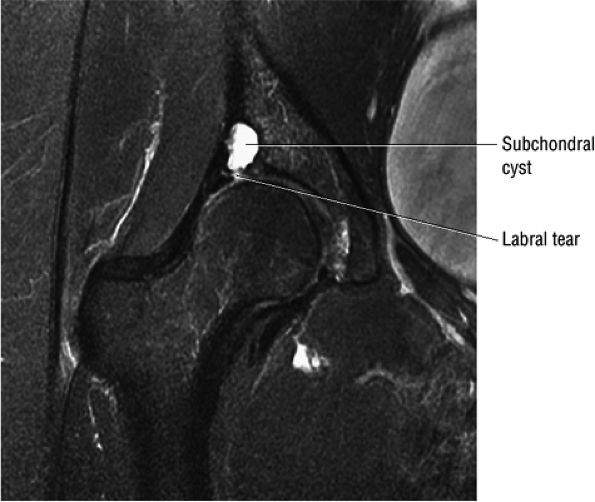

Degenerative arthritis of the right hip, with severe anterior superior chondral loss, anterior and superior labral tearing, an adjacent large paralabral cyst, and subchondral cystic changes involving the anterior acetabulum

-

Dysplastic bump in the anterolateral femoral head-neck junction associated with cam-type femoroacetabular impingement

No evidence of avascular necrosis